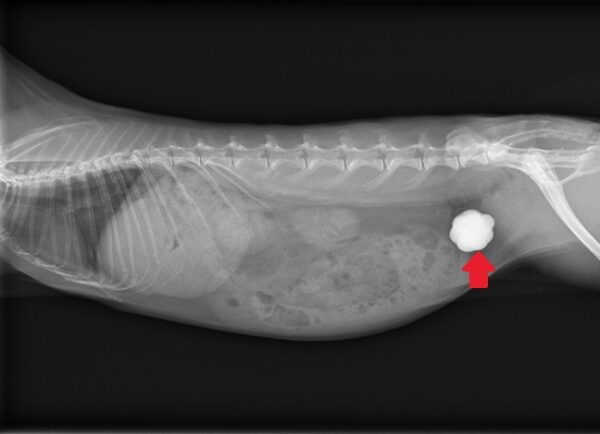

ウサギのカルシウム代謝は非常に独特で、食事から摂取したカルシウムの多くを尿中に排泄する特徴があります。そのため、カルシウム分の多い食事を続けているウサギは、膀胱内に結石ができやすいです。(写真⑥)